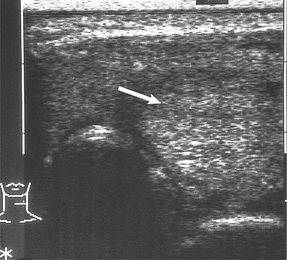

SOLITARY MASSES

Diagnostic imaging of the thyroid gland may be performed with 99mTc, which localises to the gland in a similar distribution to iodine (Fig. 17.29). ‘Cold’ lesions (which do not take up the radio-isotope) may be cysts or solid tumours; these can be distinguished by ultrasonography, which is gradually superseding 99mTc scanning (Fig. 17.30), or by fine-needle aspiration cytology. Cytology enables a pre-operative diagnosis of thyroid neoplasia to be made and has revolutionised the management of thyroid nodules.

image

Fig. 17.30 Ultrasound scan of thyroid. There is a solid solitary nodule (arrowed) which may be neoplastic.